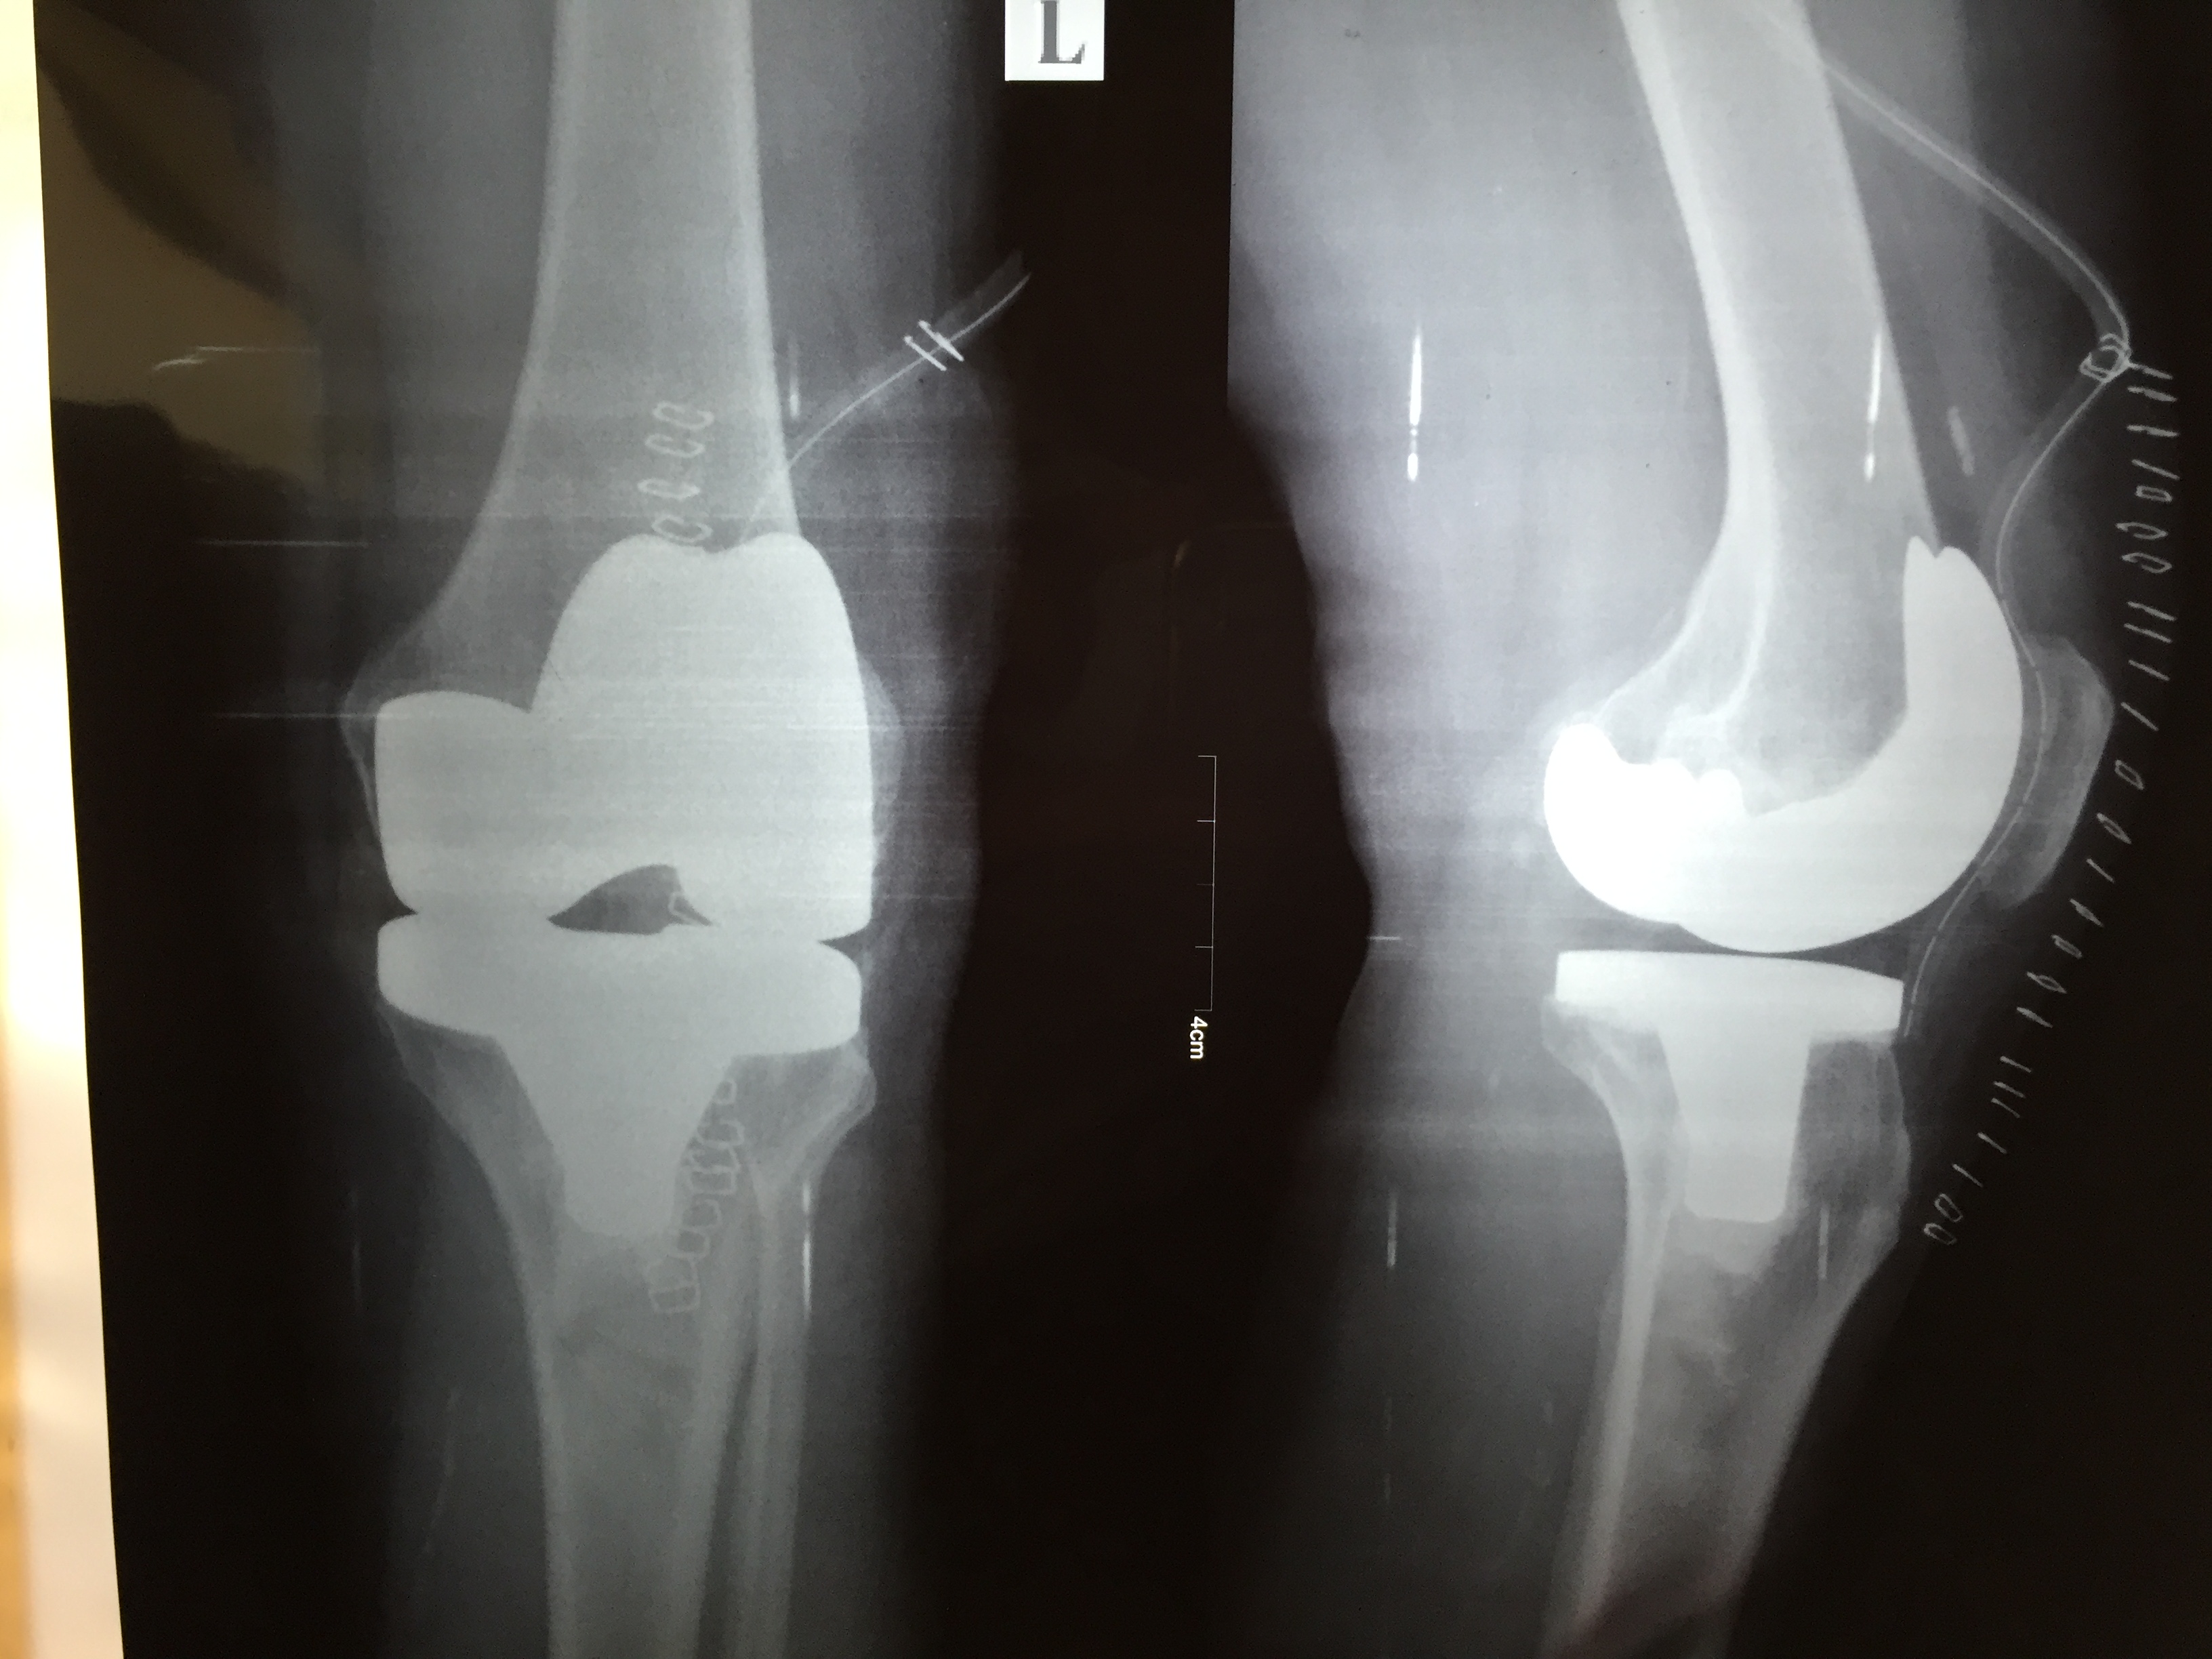

Total Knee replacement is a surgical procedure in which parts of an arthritic or damaged joint are removed and replaced with a metal, plastic, or ceramic device called a prosthesis. The prosthesis is designed to replicate the movement of a normal, healthy joint.

What is the Procedure?

Total joint replacement surgery takes a few hours. The procedure is performed in a hospital or outpatient surgery center.

During the surgery, the damaged cartilage and bone is removed from your joint and replaced with prosthetic components made of metal, plastic, or ceramic. The prosthesis mimics the shape and movement of a natural joint.

What is the advantage?

The majority of patients are able to perform daily activities more easily after joint replacement surgery. Most people can expect their joint replacement to last for many years, providing them with an improved quality of life that includes less pain, along with improved motion and strength that would not have been possible otherwise.